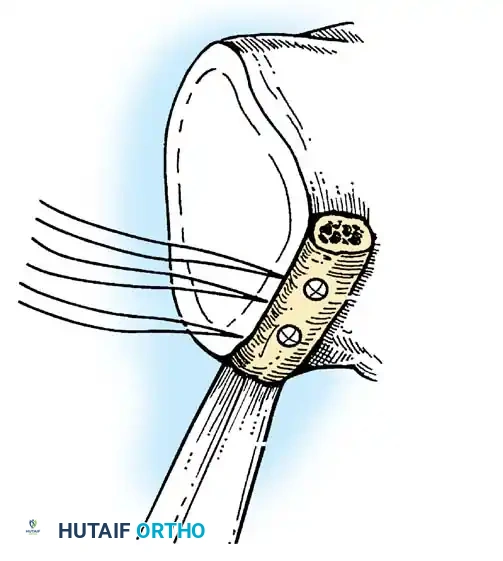

Capsular Shift and Closure

To address capsular redundancy, an inferior capsular shift is performed.

- The arm is positioned in 30 to 45 degrees of abduction and 20 degrees of external rotation.

- The inferior capsular flap is advanced superiorly and laterally, tensioning the IGHL complex. The sutures from the anchors are passed through the shifted capsule and tied.

- The superior flap is then brought down over the inferior flap in a "pants-over-vest" fashion to reinforce the anterior wall and close the rotator interval.